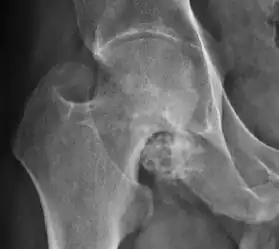

Plain radiography allows us to categorize the hip as normal or dysplastic or with impingement signs (pincer, cam, or a combination of both). Besides these, pathologic processes like osteoarthritis, inflammatory diseases, infection, or tumors can also be identified (Figure 1).[1]

Figure 1.

Synovial chondromatosis can be confidently diagnosed by X-ray when calcified cartilaginous chondromas are seen. However, other synovial proliferative processes, such as pigmented villonodular synovitis, require MRI for accurate diagnosis, although noncalcified synovitis can be suspected in radiographs by indirect signs, such as soft tissue swelling and/or erosions in the femoral head, femoral neck, or acetabulum (Figure 7).[1]

X-ray of synovial chondromatosis.[1]

CT of synovial chondromatosis.[1]